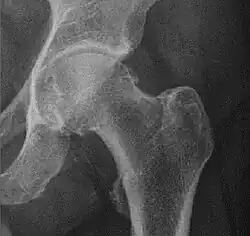

Crowe classification

In 1979 Dr. John F. Crowe et al. proposed a classification to define the degree of malformation and dislocation. Grouped from least severe Crowe I dysplasia to most severe Crowe IV.[13] This classification is very useful for studying treatment results.

Rather than using the Wiberg angle because it makes it difficult to quantify the degree of dislocation they used 3 key elements to determine the degree of subluxation: A reference line at the lower rim of the "teardrop", junction between the femoral head and neck of the respective joint and the height of the pelvis (vertical measurement). They studied anteroposterior pelvic x-rays and drew horizontal lines through the lower rim of a feature called "teardrop". The distance between this line and the middle lines of the junction between femur head and neck gave them a measure of the degree of femur head subluxation. They further established that a "normal" diameter of the femur head measures 20% of the height of the pelvis. If the middle line of the neck-head junction was more than 10% of the pelvis height above the reference line they considered the joint to be more than 50% dislocated.[13]

The following types resulted:[13]

Crowe I | Femur and acetabulum show minimal abnormal development. | Less than 50% dislocation |

Crowe II | The acetabulum shows abnormal development. | 50% to 75% dislocation |

Crowe III | The acetabula is developed without a roof. A false acetabulum develops opposite the dislocated femur head position. The joint is fully dislocated. | 75% to 100% dislocation |

Crowe IV | The acetabulum is insufficiently developed. Since the femur is positioned high up on the pelvis this class is also known as "high hip dislocation". | 100% dislocation |